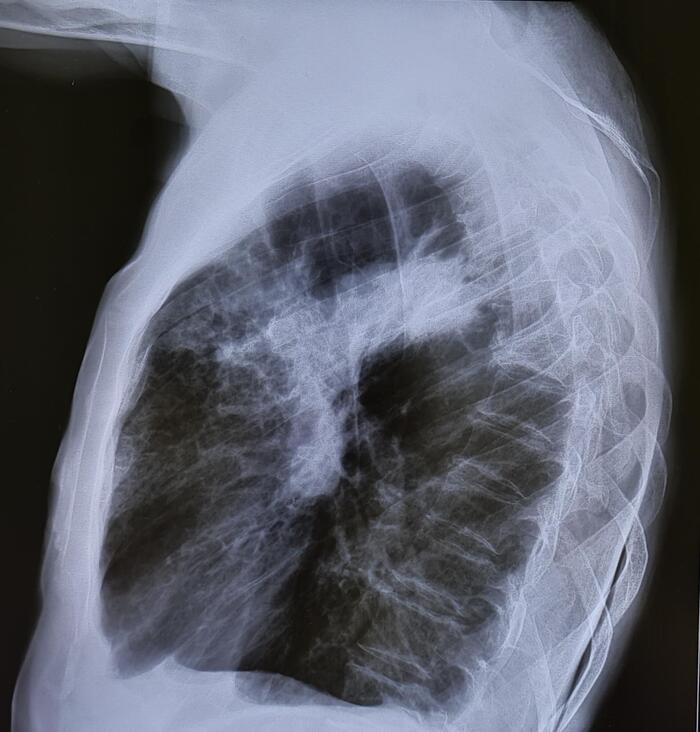

Двустороннее ассиметричное скопление жидкости плотностью +10-20 HU,с максимальной толщиной выпота справа -42мм,слева-16мм(ориентировочный объем жидкости справа-530мл,слева-157мл).

Заключение: Двусторонний гидроторакс, средний по объему-справа, малый-слева.